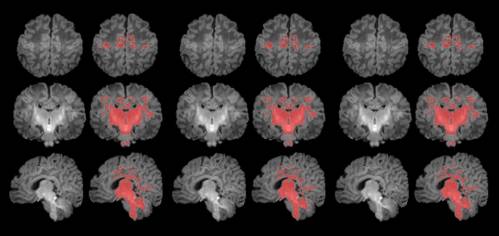

neprosina

Estructura tridimensional del precursor de la neprosina. / IBMB